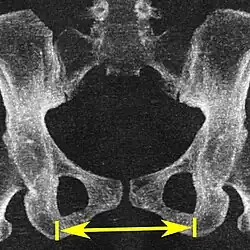

| Intertuberous diameter |

![]() Axial plane |

The closest bony points of the ischial tuberosities | 10 to 12 cm.[6] | |